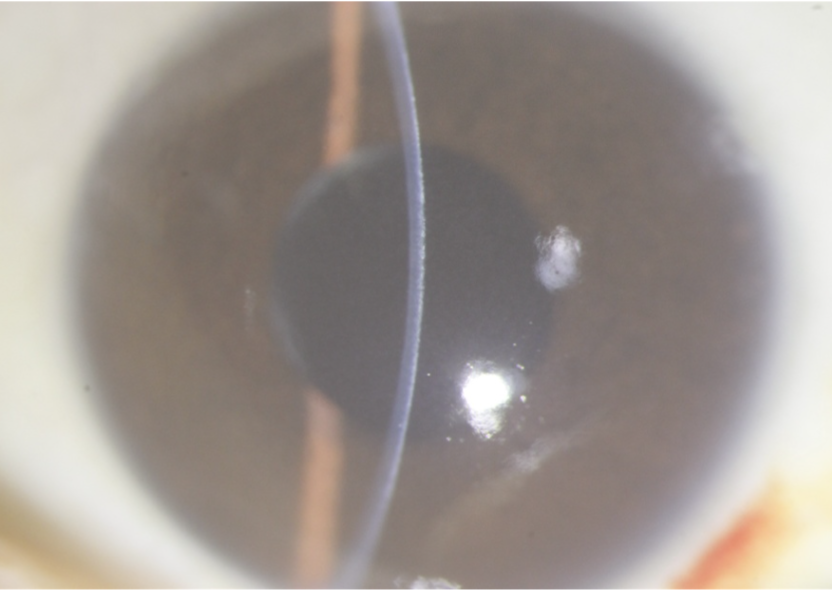

每年3月6日是世界青光眼日,今年3月10日—3月16日是第17个世界青光眼周,本次主题:共管慢病青光眼,留得光明恒久远。东莞光明眼科医院青光眼科副主任医师陈奕辉表示,青光眼是不可逆性致盲眼病,除了保持良好的生活习惯和用眼习惯外,患者每年定期检查眼压必不可少。出现眼睛胀疼、视力下降、看东西出现“彩虹光晕”等情况时,立刻前往专业的医院就诊。 01 借右眼失明经验,左眼就诊及时 “我儿患有1型糖尿病,被并发症折磨了多年,现在眼睛都看不见了,他今年才25岁,之后怎么办啊。”王某母亲眼中闪烁着泪光。陈奕辉给王某进行了专业的眼科检查,发现王某的右眼无光感;左眼视力0.25,眼压68mmHg(正常眼压在10-21mmHg),门诊诊断为“左眼新生血管性青光眼”并收入院治疗。 “你这是在高血糖的状态下,眼部发生一系列的病变,导致眼压升高,进而引起青光眼。”陈奕辉解释道。青光眼是一组以视神经凹陷性萎缩和视野缺损为共同特征的疾病,病理性眼压增高是其主要危险因素,是全球第一位不可逆性致盲眼病。 早发现早治疗是青光眼防治的关键。“我的右眼就是多年前因青光眼而导致失明的,之前发病没有重视,想着多休息就好了,结果越来越严重,后面去医院已经晚了,右眼失明且无法复明。”王某对此很懊悔,“这次吸取了右眼的经验,及时就医。” 02 引流阀植入术开辟“新通道” 青光眼一经诊断,往往需立即治疗。陈奕辉表示:“治疗青光眼的目的是有效和及时地控制升高的眼压,阻止视神经进一步损害。但目前各种治疗措施主要起到降低眼压的作用,已经发生的视神经损害无可挽回。” 患者左眼术前(左)和术后(右)眼部情况对比 青光眼如何治疗?青光眼可以通过药物、激光、手术等方式治疗。手术方式虽有多种,但手术目的都是为了打开眼球内房水循环的新通路。“根据检查结果显示,王某眼球情况特殊,正常手术的部位均发生粘连。”陈奕辉介绍道,“经讨论,决定在鼻下方行左眼青光眼引流阀植入,难度较大。”但在陈奕辉精湛的手术技术下,王某的手术顺利,左眼眼压降至17mmHg,术后恢复较好。 患者需保持良好的生活习惯 “青光眼患者需要终身治疗和随诊,但部分患者因对疾病认识不足而影响治疗。”陈奕辉提到,部分患者会因为使用眼药水“无法提高视力”,或使用降眼压眼药水“感觉不舒服”等原因而自行停药,等视力降至影响生活时再来检查,已经无法挽救已受损的视功能。 副主任医师陈奕辉给患者做手术中 因此,陈奕辉建议青光眼患者应定期检查,每月至少一次到医院测量眼压,每3月做一次全面检查,尤其是视力、视野、视盘的检查;注意观察眼睛情况变化,突然剧烈眼痛、头痛伴恶行呕吐,或视力下降、视物模糊,或其他自觉症状严重不适时,请及时就诊。 高危人群建议定期检查 青光眼早期难以发现。一旦发现眼胀、眼痛、视物不清,伴有头痛、恶心、呕吐等症状时,及时就医。陈奕辉表示,除了糖尿病会继发青光眼外,高度近视、40岁以上、有家族青光眼病史、高血压、眼外伤病史、高眼压等人群也是青光眼高危人群,建议每年到医院接受眼健康检查,监测眼压和视野。 最后,陈奕辉介绍了手指自测眼压的小方法:“眼睛向下看,以两手食指尖置于上睑,交替按压眼球,借指尖触测,若眼球硬度同鼻尖,则说明眼压正常;眼球硬度同额头,则眼压较高;眼球硬度同嘴唇,则眼压较低。”